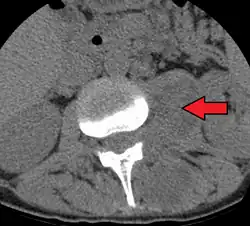

Psoas abscess

| Paraspinal abscess in the psoas muscle | |

Psoas abscess is a collection of pus (abscess) in the iliopsoas muscle compartment.[1][2][3] It can be classified into primary psoas abscess (caused by hematogenous or lymphatic spread of a pathogen) and secondary psoas abscess (resulting from contiguous spread from an adjacent infectious focus).[3]